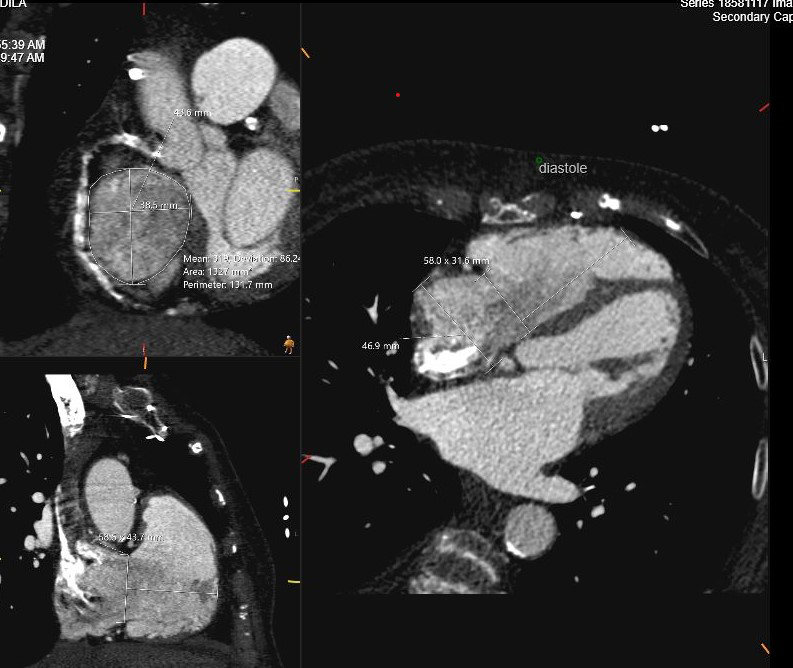

Fig. 6.

Cardiac CT assessment of TR. Using tricuspid valve protocol during administration of intravenous contrast in preparation for transcatheter TV replacement. Measurements include TV annulus in systole and diastole, RV height perpendicular to TV plane and RA height. TV, tricuspid valve; CT, computed tomography.